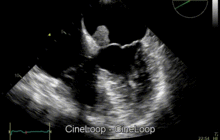

- Echocardiogram and Doppler study